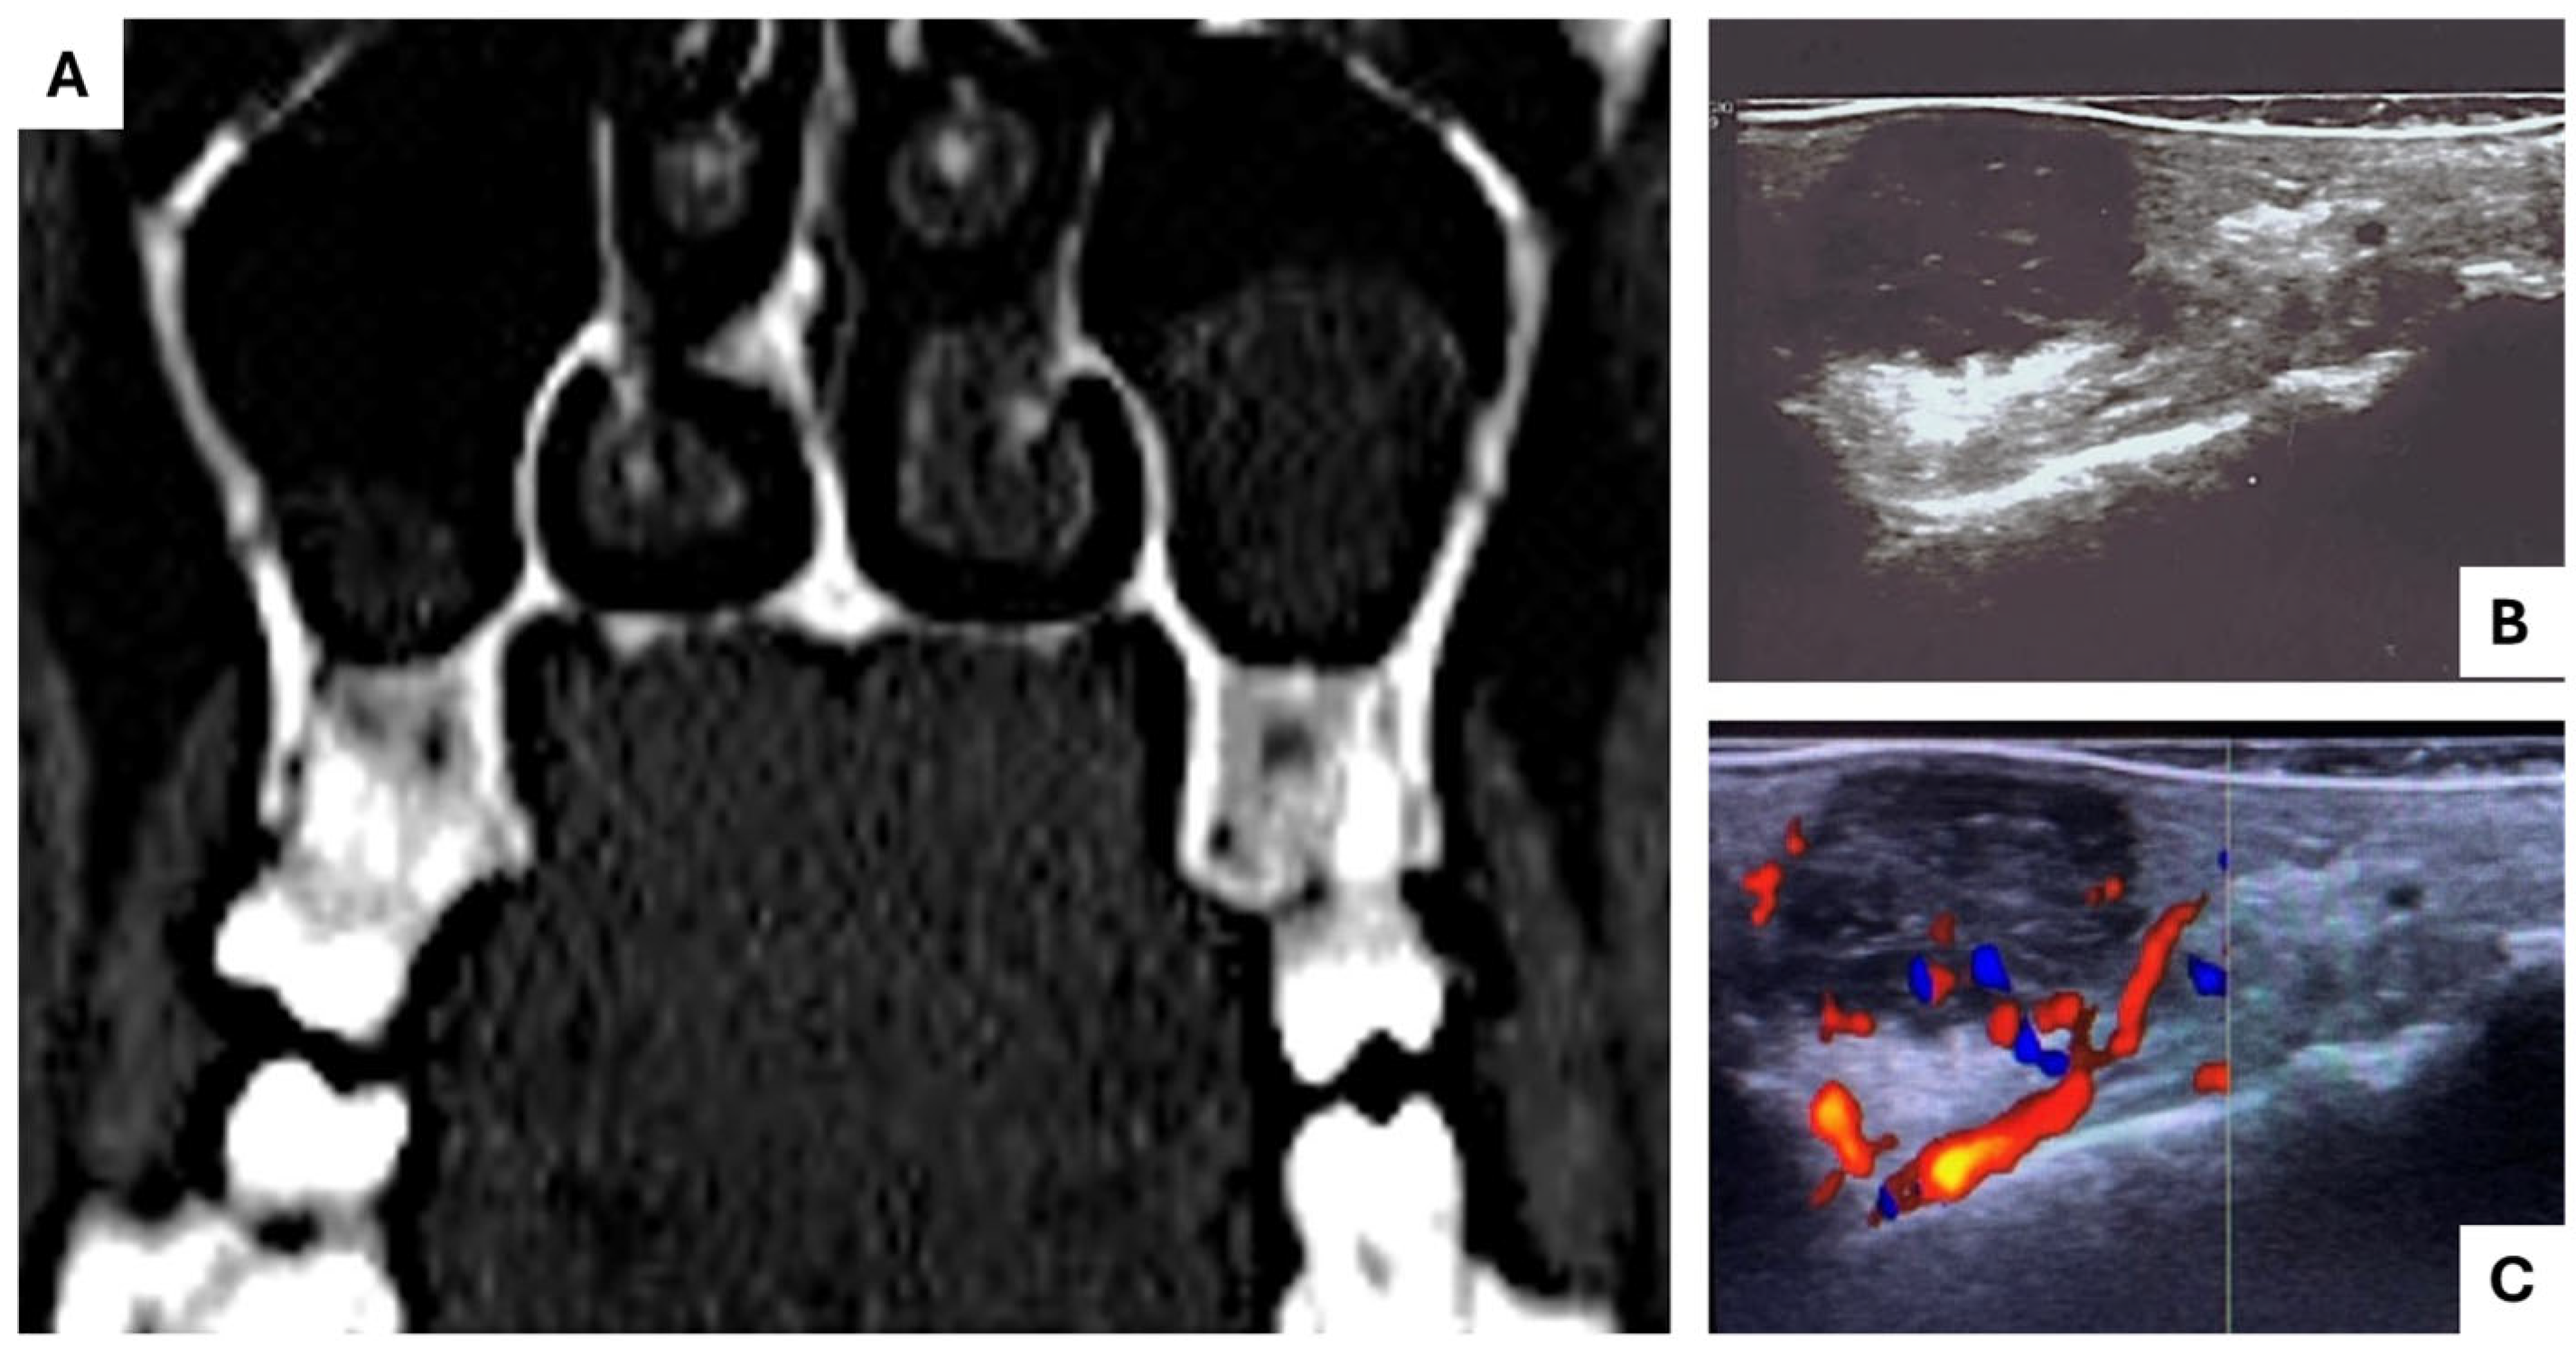

- Intraoral HDUS: Performed using a GE Logic 9 ultrasound device (General Electric Healthcare, Chicaco, IL, USA) with an 18 MHz linear probe (hockey stick-shaped); to enhance the image quality in the grayscale and color Doppler modes, the probe was enclosed in a latex protection filled with US gel to eliminate air bubbles.